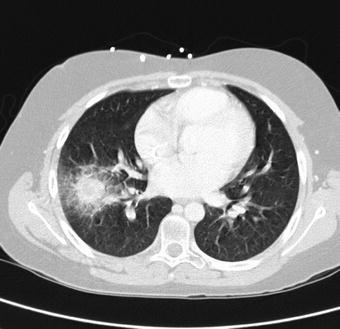

Patients with persistent FN are at increased risk for invasive fungal disease (IFI) and are usually started on antifungal therapy at 5–7 days of fever. In adult practice, the standard of care is now to perform a CT of the chest (+/– sinuses) at the time of starting antifungal therapy. This practice leads to an earlier diagnosis of IFI, in particular with moulds, such as invasive pulmonary aspergillosis (IPA). In IPA, patients characteristically develop a ‘halo-sign’ (Fig. 1) on CT early in the first week of the disease (Caillot et al., 1997). In a study of patients with IPA, 95% of subjects had characteristic halo-sign lesions on HRCT when chest X-ray showed either normal (29%) or non-specific findings (71%) (Hauggaard et al., 2002). It is important to stress that the halo-sign is only present in the first week in IPA, and then progresses to be a non-specific infiltrate if the CT is performed at a later stage. Caillot and colleagues have also demonstrated the benefit of using early CT, along with early surgery and antifungals in IPA. Using this approach, they report a cure rate of about 84%, compared with a success rate of 40–50% usually reported in the literature (Caillot et al., 1997, 2001).

Fig. 1.

CT scan of the chest in a 12-year-old patient with AML and a history of long-standing neutropenia with 5 days of fever. The lesion in the right lung displays the characteristic ‘halo-sign’ feature of a macronodule surrounded by an area with a ground glass appearance. The patient was treated with intravenous followed by oral voriconazole with good clinical response